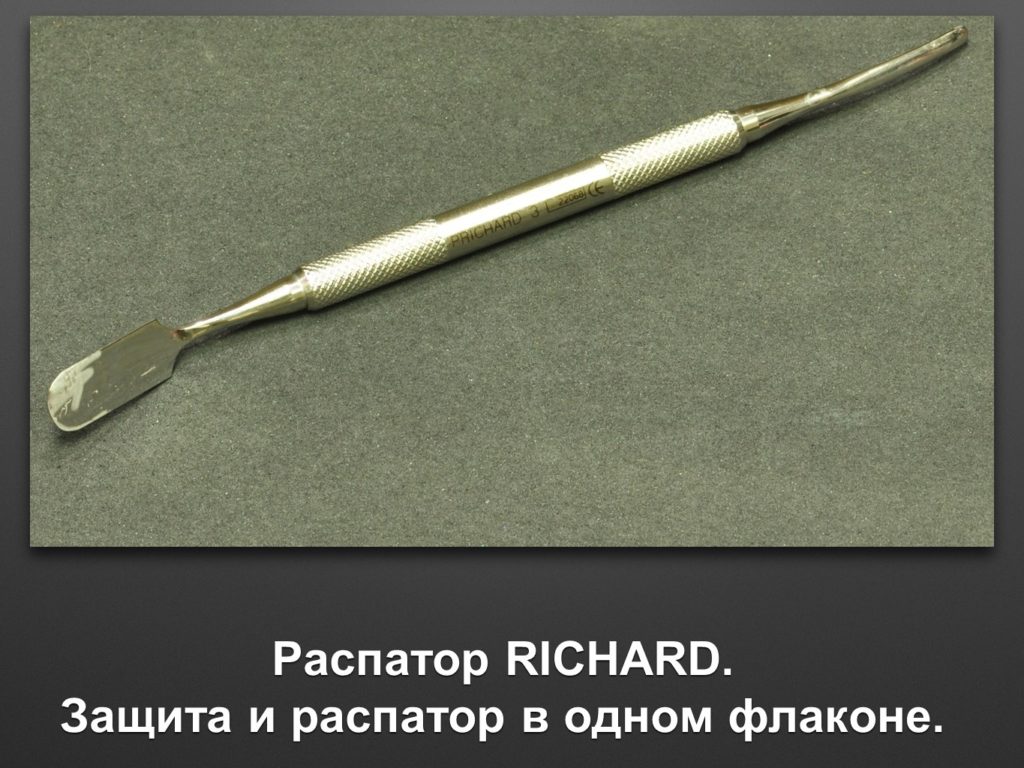

"Выстраданные" наборы инструментов

Все ниже перечисленные инструменты можно приобрести на сайте kohlermed.ru или связаться с нашим менеджером по тел 499-5179401

Все ниже перечисленные инструменты можно приобрести на сайте kohlermed.ru или связаться с нашим менеджером по тел 499-5179401